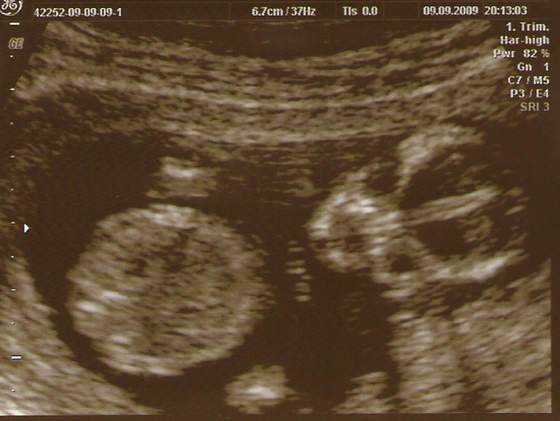

Z prawej strony noga, z lewej strony noga (mniejsza bo nia machnal) a miedzy nimi COS :-)

Zobacz załącznik 165064